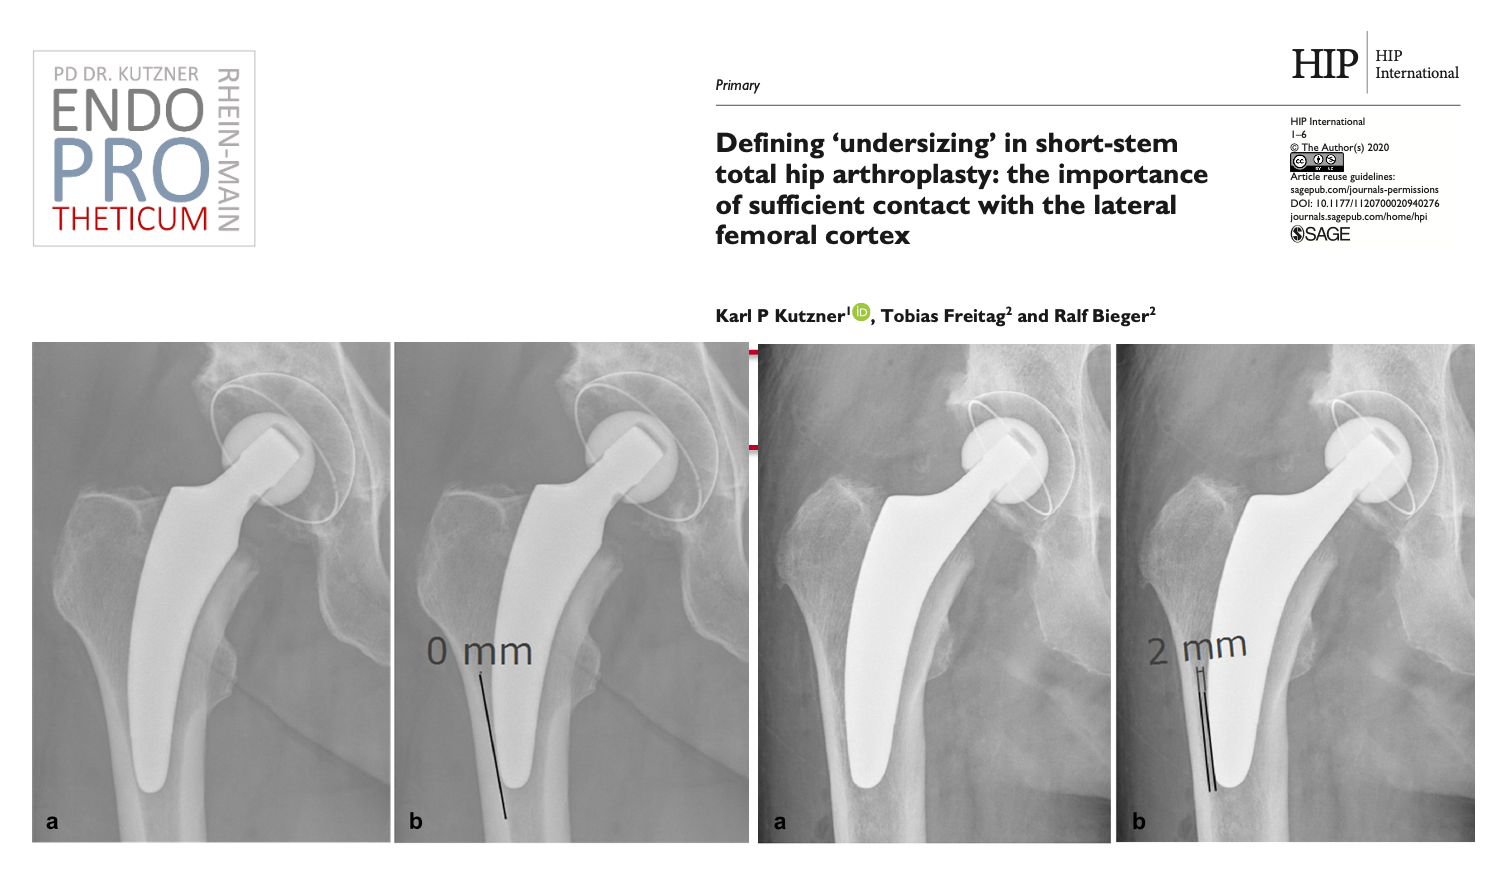

Le concept de tiges courtes modernes guidées par le calcar dans l'arthroplastie de la hanche vise à la reconstruction précise de la géométrie anatomique individuelle de la hanche. Une technique d'implantation douce pour les os et les tissus mous est utilisée en association avec une mise en charge physiologique dans la partie du fémur proche de l'articulation afin de préserver l'os à long terme.